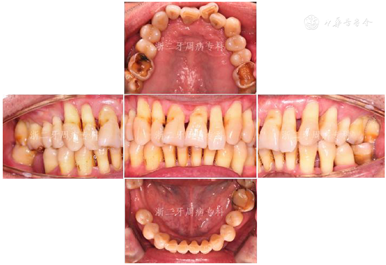

2011年4月:牙周基础治疗后3年复诊。患者口腔卫生维护佳,牙周状况良好,牙龈色粉,无明显红肿,口内未见明显结石与软垢(图13),牙齿松动度牙周袋进一步变浅,PD≥7 mm位点消失,4~6 mm的位点数进一步减少,仅有6个位点,BOP(+)%仅为6.5%(图14)。全口曲面体层X片示:牙槽骨硬骨板较明显,牙槽骨无进一步吸收迹象;37、46缺牙区牙槽骨高度无明显降低(图15)。检查结果显示,患者牙周状况已经稳定。予以牙周维护治疗、复发危险评估,评估结果为中度(图16),嘱患者继续保持口腔卫生,随访时间可延长至9~12个月。

2021年8月:牙周基础治疗后13年复诊,患者口腔卫生维护佳,牙周状况较上一次复诊牙龈色粉,无明显红肿,口内下前牙区可见少量龈上结石(图23),松动度进一步改善,全口BOP(+)%进一步下降至15.4%,但36仍可探及较深牙周袋,近中探诊能触及根尖(图24)。X线片示:与2018年12月比较,36近中根牙槽骨进一步吸收,吸收已达根尖,而全口其余位点牙槽骨没有明显出现进一步吸收现象;14根尖可见低密度影(图25)。口腔锥形束CT(CBCT)示:36近中根牙槽骨吸收至根尖,牙齿与骨面基本分离,舌侧骨壁缺失,颊侧骨壁较低(图26)。本次行复发危险评估结果示高复发危险度,但与上次评估相比,由3个高度危险因素转变成2个高度与1个中度,情况有所好转(图27)。

牙周基础治疗是治疗牙周炎最基本也是最有效的手段,是任何牙周病患者治疗成功的关键[2]。本例患者发生重度牙周炎的主要原因为口腔卫生差,菌斑控制不佳,早期出现刷牙出血等牙周炎早期症状时未予重视。初诊时患者全口牙齿松动,牙龈炎症严重,仅经过彻底的牙周基础治疗,包括口腔卫生指导、龈上洁治、龈下刮治与根面平整等,去除菌斑和牙石等局部刺激因素,配合牙周固定,使牙齿松动度改善,牙周袋深度明显降低,有效控制了牙龈组织炎症,同时出现牙槽骨修复。随访13年来,除早期拔除的37、46外,绝大多数Ⅱ~Ⅲ度松动、牙槽骨吸收至近根尖、愈后无望的患牙得以长期保留,功能恢复良好。46对应位点牙槽骨部分修复再生(图28)。患者13年来探诊深度水平随着基础治疗及维护治疗的进行不断改善,目前基本维持稳定(图29)。